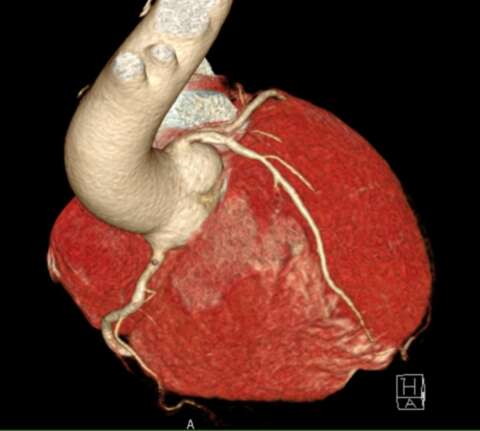

Weiterhin können erste Veränderungen mit diagnostischen Früherkennungsmethoden wie moderner Bildgebung erkannt werden (Abb. 3). Hier ist wissenschaftlich insbesondere das mittels Scores festgestellte mittlere Risiko im mittleren Alter eine prädestinierte Gruppe von gesundheitsorientierten Menschen. Bei niedrigem Risiko bleibt eine weitere Früherkennung weniger effektiv, da meist keine relevanten Befunde provoziert wurden. Ein höheres Risiko ist bereits sehr hoch und lässt keine wesentlichen therapierelevanten weiteren Erkenntnisse durch weitergehende Diagnostik erwarten.

Abb. 3. (Bildmaterial der EPC GmbH – European Prevention Center). Dargestellt ist ein Kalkplaque am Abgang der vorderen absteigenden Herzkranzarterie in einer Herz-Computertomographie (CT) eines 56-jährigen Check-Up-Individuums ohne jegliche Symptomatik.